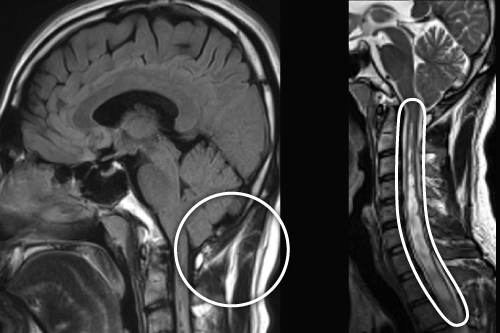

キアリ奇形

咳やいきみで誘発される咳嗽性頭痛の約40%は頭の中の病気があるともいわれています。咳嗽性頭痛の代表例がキアリ奇形です。小脳が下方に下垂しており、時に脊髄空洞症を伴います。

低頭蓋内圧性頭痛・脳脊髄液漏出症

起立性頭痛が雷鳴頭痛として発症することがあります。低髄圧もしくは脳脊髄液漏出による起立性頭痛は、頸部痛、耳鳴、聴力変化、光過敏や悪心を伴うことがあります。